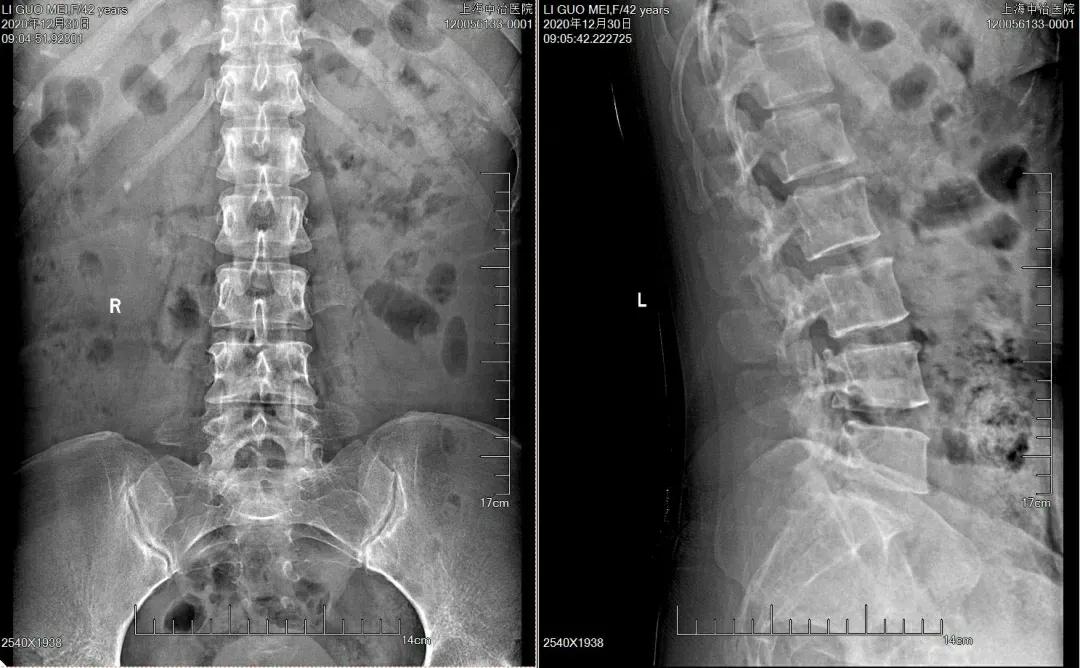

X线片

正位片可显示腰椎侧弯;椎间隙变窄或左右不等,患侧间隙较宽。侧位片显示腰椎生理前屈减少或消失,发生椎间盘突出的椎间隙后方宽于前方;后期椎体边缘有骨赘形成,关节突关节退变,上、下关节突交错,下关节突变尖插入椎间孔,使椎间孔变小。